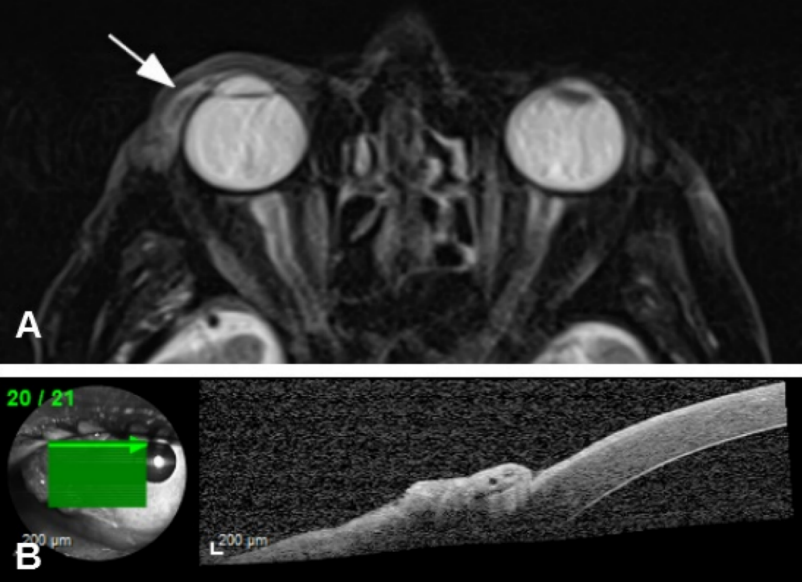

A 90-year-old man was referred to us with a mass in his right eye that had first been noticed three months earlier and had been growing progressively since then. VA was 20/200 in the right eye and hand movement in the left eye. Slit-lamp examination revealed a gelatinous temporal conjunctival mass (7 mm long, 10 mm wide) with dilated superficial vessels (Figure 4A [Fig. 4]). Fundus examination showed age-related macular degeneration (AMD) in both eyes. Ocular movements were affected in the form of abduction limitation in the right eye (Figure 4B [Fig. 4]). An incisional biopsy was performed and a moderately differentiated SCC was confirmed (Figure 5 [Fig. 5]). Magnetic resonance imaging (MRI) showed malignant infiltration of the lateral rectus muscle (Figure 6A [Fig. 6]). Anterior segment optical coherence tomography (AS-OCT) displayed a hyperreflective lesion which involved the conjunctival tissue and spread over the corneal surface (Figure 6B). Due to the advanced stage of the tumor, an exenteration or radiotherapy treatment was offered, but the patient rejected both. After five months, the tumor had progressed and involved ocular globe tissues and soft periorbital structures (Figure 7 [Fig. 7]). The patient died due to metastatic disease nine months after the initial diagnosis.

Figure 6: A) Magnetic Resonance Imaging showed lateral rectus muscle involvement. B) Anterior Segment – Optical Coherence Tomography (AS-OCT): a hyperreflective lesion involving conjunctival tissue and spread over corneal surface